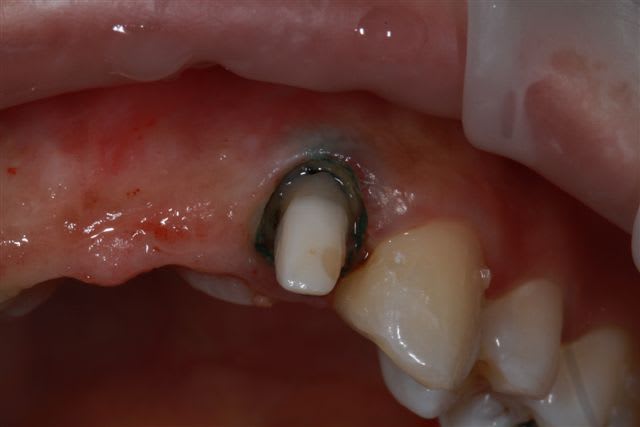

Donc dans un premier temps,je décide d'essayer de retraiter 12/22, de toute façons ça ne peut pas être pire que ce qui tiens depuis 10 ans... enfin 12 mobilité quasiment 3.

ensuite Srew post (bouh...) et résine, afin de pouvoir poser un provisoire et réfléchir à l'avenir du parodonte...car il va y avoir un problème quelle que soit la solution choisie.

013copier i9y3do - Eugenol

Img 1857r cxv5g1 - Eugenol

003copier gsgoia - Eugenol

012copier yso0mb - Eugenol

002copier mphusk - Eugenol

la suite

reconstitution, taille pour empreinte et provisoire (pas beau mais il sera remplacé)